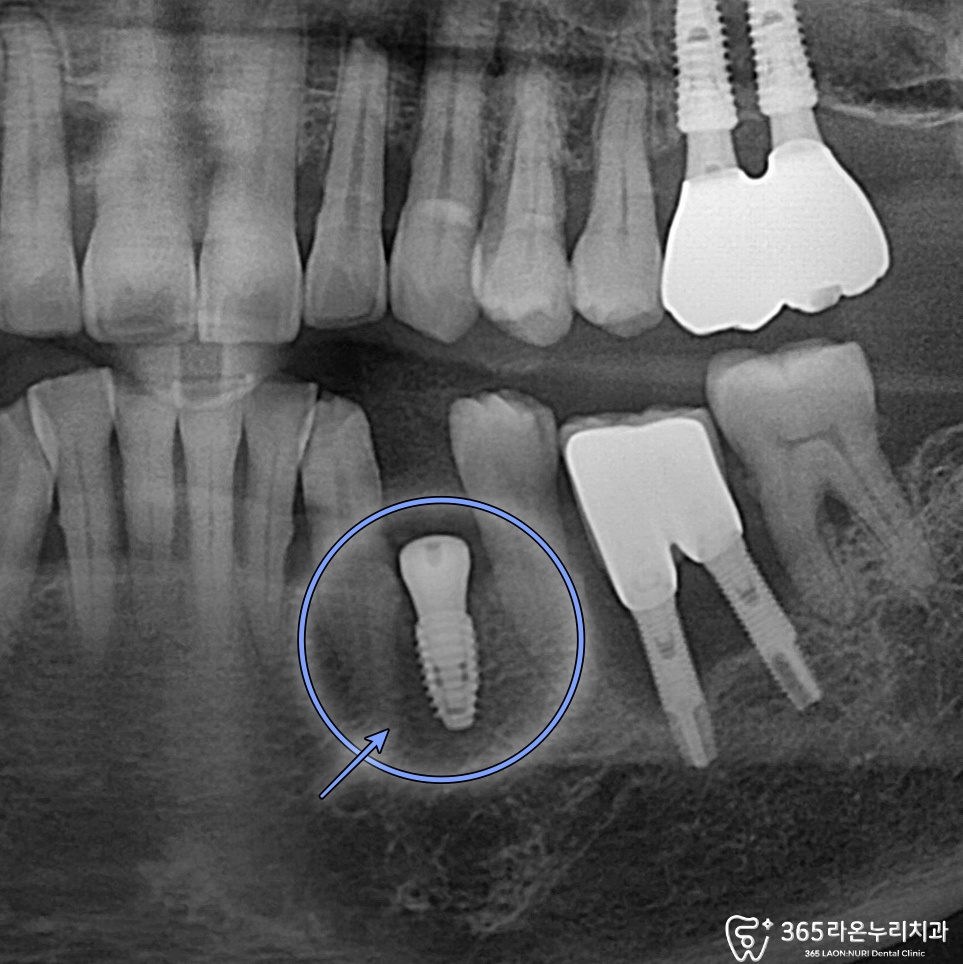

2025.02.20

수청동 치과 에서

식립된 모습을 보면

넓지 않은 공간에

잘 심겨져 있는 모습을 볼 수 있는데요.

모든 진료가 끝난 후에는 최종 점검을 위해

다시 x-ray 사진을 찍습니다.

2025.04.30